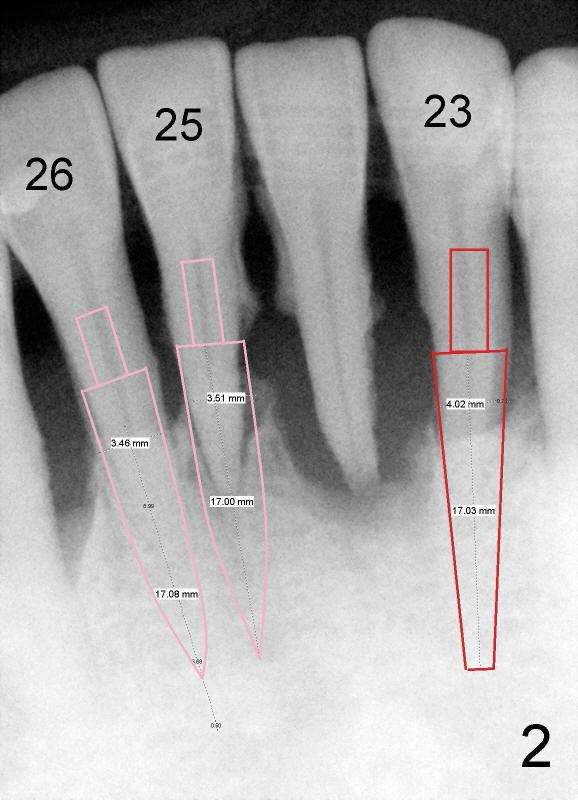

Dear Drs. Dunson and Borgner: Thank you for giving me invaluable advice, which I will use for future cases. In fact the teeth #23 and 25 were extracted last Thursday. The mesiodistal width of both roots is 3.5 mm, while the buccolingual 5 mm. It is presumed that a 4 mm implant should not perforate the buccal plate. On the other hand, the relatively large implant should fill most of the socket. Upon implant placement, the buccal plate does not feel to bulge or perforation, particularly in apical aspect, by tactile sensation. There is separation between the root of the tooth #22 and the pilot drill (1.5 mm) at the site of #23 whereas the space is limited between the pilot drill (2 mm) at the site of #25 and the root of the tooth #26. As Fig.4 and 5 indicate, a 4x17 mm one-piece implant is placed at the site of #23 and 3.5x17 mm at #25. A temporary bridge is fabricated between #23 and 25 and splinted to #22 and 27 (Fig.6). Since the abutment of the 4x17 mm one-piece implant is not tall, parallelism is not an issue after initial prep. The tooth #21 is missing. Do we still have to splint between #20 and #29 in one piece lingually?